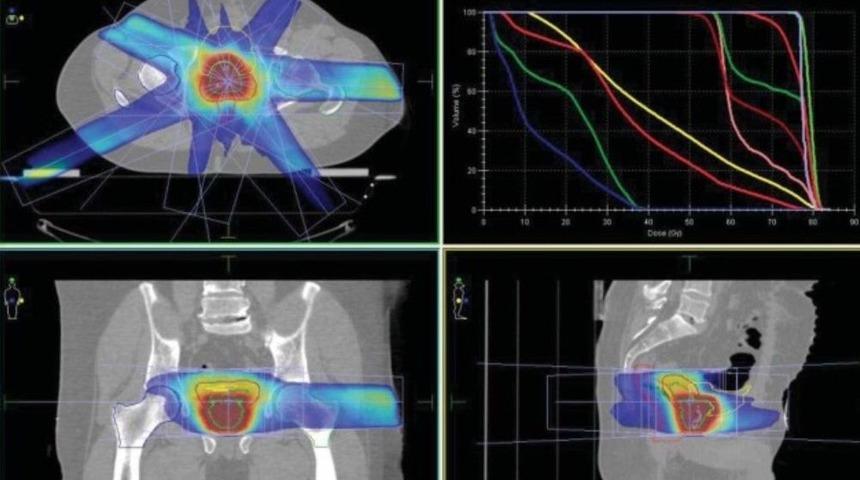

Radyasyon Onkolojisi Prof. Dr. Ali Aydın Yavuz, prostat kanserinin ışınla tedavisinde (radyoterapi) yeni bir yöntemle kanser tedavisinin hem hızlandığını hem de çok avantajlı sonuçlar elde edilebildiğini belirtti.Antalya’daki Onko Talya Kanser Kliniği Uzmanlarından Radyasyon Onkolojisi Prof. Dr. Ali Aydın Yavuz, "En son Avrupa Radyoterapi ve Onkoloji Derneği (ESTRO) kongresine adeta damga vuran çok önemli bir çalışmada bin 200 prostat kanseri tanısı almış hasta ile yapılan araştırma sonuçlarına göre, günlük dozlar yükseltilerek çok kısa sürede verilen radyoterapi tekniği sayesinde prostat kanserli hastalar için gayet etkili ve emniyetli sonuçların elde edilebildiği olduğu ortaya konuldu" dedi."Kısa süren bir tedavi"Prof. Dr. Yavuz, "Ultrahipopraksiyone radyoterapi olarak da adlandırılan bu hızlandırılmış radyasyon tedavisi, 8 hafta kadar süren standart bir radyoterapiye kıyaslandığında, toplamda 2.5 hafta süren, yani çok daha kısa süren bir tedavidir. Radyoterapinin prostattaki kanser hücrelerini yok edebileceğini ve ameliyat ve hormon tedavisine göre ciddi bazı avantajları olduğunu zaten biliyoruz, zira cerrahiye göre iktidarsızlık veya idrar-gayta kaçırma olasılığı radyoterapi ile çok daha düşük. Bununla birlikte, radyoterapi pahalı cihazlar, kalabalık bir uzman ekibi gerektirir ve hastalar tedavi için bir bekleme listesine alınmak zorunda kalınabilir. Bu çok hızlandırılmış (ultrahipopraksiyone) radyoterapi, hastalara hem zaman, hem de maliyet tasarrufları için bir çok fayda sunar, bu yüzden standart radyoterapi kadar güvenli ve etkili olup olmadığının test edilmek istenmiş olması tüm kanser uzmanlarının bu çalışmaya ilgisini çekmeye yetmiştir" ifadelerini kaydetti."Çok hızlanmış radyoterapinin sonuçları başarılı"Çalışmanın İsveç Umea Üniversitesi, Radyasyon Bilimleri ve Kanser Merkezi Merkezi bölümünce sunulduğunu belirten Prof. Dr. Yavuz, "Araştırmacılar, Temmuz 2005 ile Kasım 2015 arasında İsveç’te 10 hastanede ve Danimarka’da iki hastanede tedavi edilen bin 200 prostat kanserli hasta ile böyle bir araştırmayı gerçekleştirdiler. Hepsi, orta veya yüksek riskli prostat kanseri teşhisi konulan, yani tedavi edilmezse vücuda yayılabilecek prostat tümörlerinin büyümesini uyarabilen erkek hormonu (testosteronu) bloke edici tedavi almamış olan hastalardan oluşmaktaydı. Hastaların yarısı (600 civarı), her biri 8 hafta boyunca (toplamda 78 Gy) yayılmış iki gray (Gy) standart radyoterapi dozuyla 39 iş günlük standart radyoterapi tedavisi aldılar. Diğer yarısı (600 civarı) ise, gün aşırı 6.1 Gy gibi yüksek günlük radyasyon dozu ile, toplamda 42.7 Gy alacak şekilde ve sadece 2.5 haftalık bir süreliğine, yani çok hızlandırılmış (ultrahipopraksiyone) radyoterapi aldı. Hastalar, kanserlerinin, prostat spesifik antijen (PSA) düzeyinin yükseldiği ve herhangi bir yan etki görüp görmedikleri ile hastalık nüksü olup olmadığı açısından tedaviler sonrası ortalama 5 yıl boyunca izlendi. Sonuçta, tedaviden 5 yıl sonra, standart (8 hafta) radyoterapi ile tedavi edilen hastaların yüzde 83.8’inde, kanserlerinin PSA değerlerinde yükselme veya nükse dair dair hiçbir belirti olmadığını saptadılar" açıklamasında bulundu."Başarılı sonuçlar"Daha önceki araştırmalardan da bahseden Prof. Dr. Yavuz, "Daha önceki bazı araştırmalar, prostat kanserlerinde ve bazı başka kanser türlerinde de günlük dozları arttırmanın ve onları 4 ile 5 hafta içinde vermenin mümkün ve emniyetli olduğunu zaten göstermiştir. Şimdi radyoterapiyi daha da yoğunlaştırabileceğimizi, her bir seansta radyasyon dozunu biraz daha da yükseltebileceğimizi, böylece tüm programın sadece 2.5 haftaya bile indirilebileceği gösterilmiş durumda. Bu çalışma, prostat kanserlerinde bu türden çok hızlandırılmış (ultrahipofraksiyone) radyoterapi adına ilk büyük hasta denemesidir ve oldukça başarılı sonuçlar elde edilmiştir" dedi.Hastalar uzun süre izlenecekProf. Dr. Aydın Yavuz, "Bu yeni radyoterapi yönteminin hastalara hem ciddi bir zaman kazandırdığı, hem de aynı zamanda radyoterapi cihaz ve personeline daha fazla boş zaman kalmasına sebep olduğu ortadadır. Bu da hem çok ciddi para tasarrufu sağlar, hem de tedavi için beklemekte olan diğer hastaların biran önce tedavilere başlanmasına fayda sağlar. Ancak, bu çok hızlı radyoterapi uygulanan hastaların daha da uzun vadede (tercihen en az 10 yıl ve sonrasında bile) hayatta kalma, nüks veya yan etki oranlarında standart radyoterapiye göre farklılıklar olup olmadığını iyice kontrol etmek için bu araştırmadaki hastaları yakinen izlemeye de devam edilmelidir" ifadelerini kaydetti.